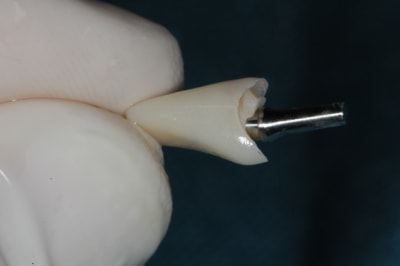

1)2) pilier impactable :ici c'est un 7° mais ils existent en 0, 7, 15 et 23°

3)4) essayage du pilier